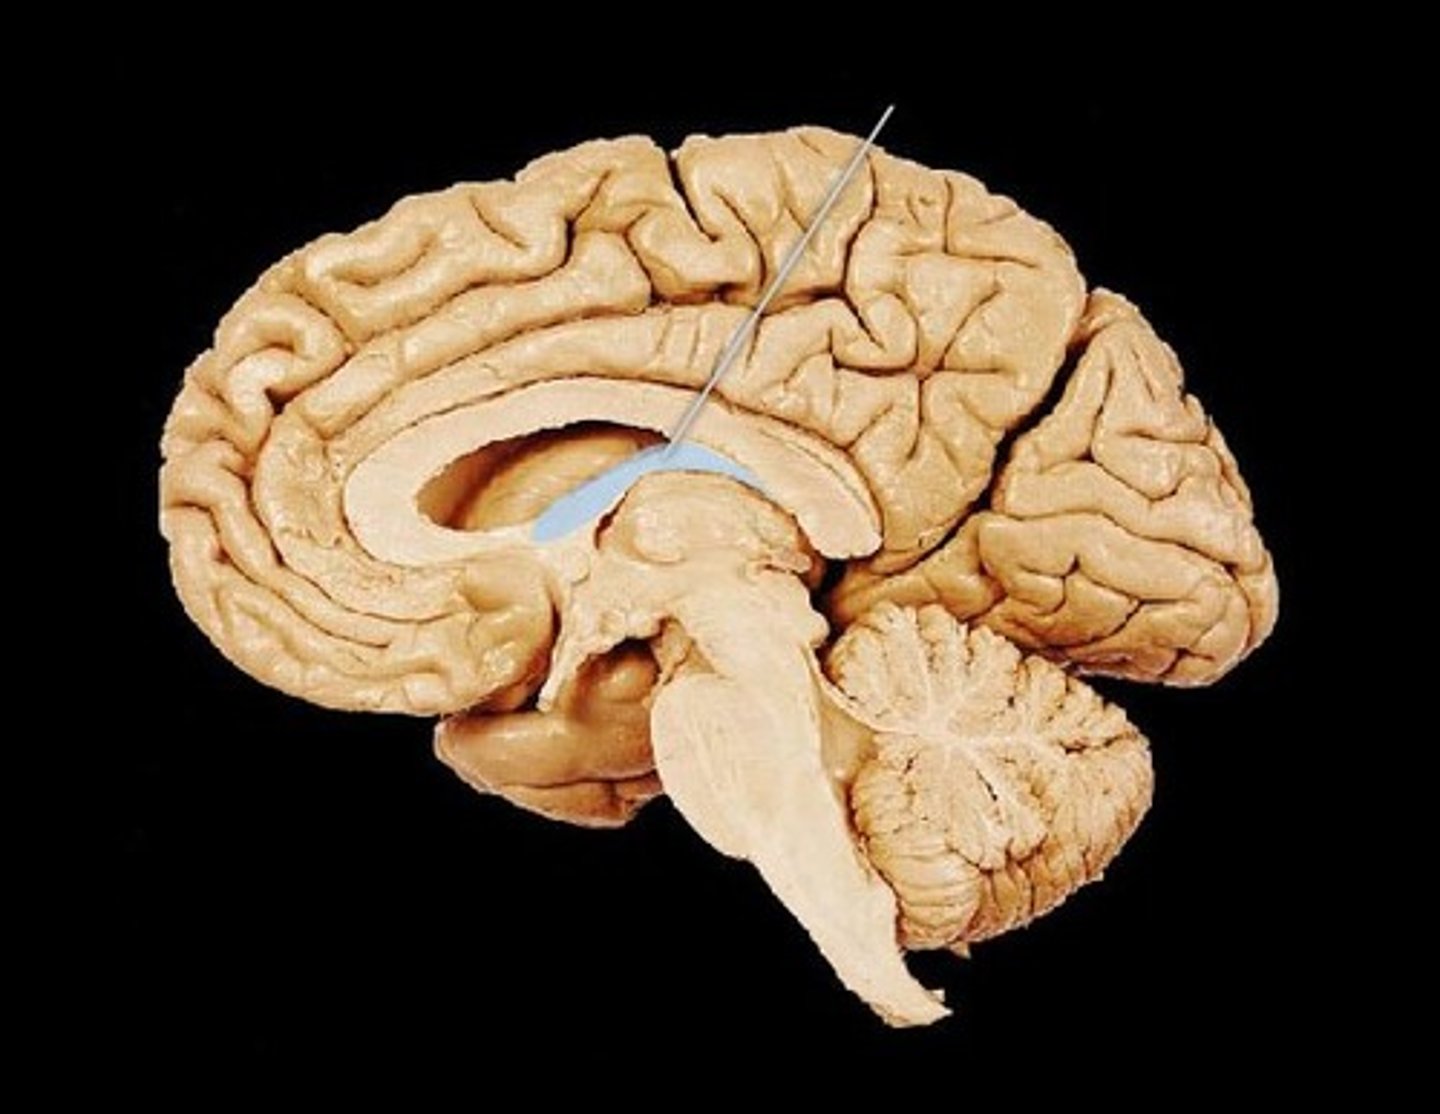

corpus callosum

fornix

cerebral aqueduct (brainstem)

corpora quadrigemina (brainstem)

fourth ventricle

hypophysis (pituitary gland)

infundibulum

pineal gland

choroid plexus (of ventricles)

third ventricle